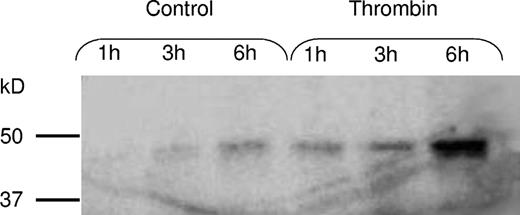

To confirm that there was an ongoing de novo synthesis of PAI-1 in platelets metabolic radiolabeling was performed. Following 35S-methionine incorporation for 1, 3, and 6 hours, immunoprecipitation was performed, which yielded a protein of the expected molecular mass of approximately 45 kD. The protein was detected both with the MAI-12 and PAI-1 (ab-1) antibodies. Figure 3A shows the results of the immunoprecipitation with PAI-1 (ab-1) of the 35S-labeled PAI-1. The increasing amount of radioactive PAI-1 over time confirms that there is an ongoing synthesis of PAI-1 in platelets. Following control immunoprecipitating without antibodies, no protein was detected (data not shown).

Metabolic radiolabeling and immunoprecipitation of platelet PAI-1. (A) Isolated platelets were incubated in the presence of 35S-methionine for 1, 3, and 6 hours. Platelet lysate and medium were immunoprecipitated with PAI-1 (ab-1) and the precipitated protein was separated with SDS-PAGE and subsequently examined by autoradiography. This yielded a protein of the expected molecular mass (approximately 45 kD), and the increasing amount of radioactive PAI-1 over time confirmed that there is an ongoing synthesis. (B) To inhibit protein synthesis, platelets were incubated for 6 hours in the presence of 1 mM puromycin, resulting in attenuated PAI-1 expression.

Metabolic radiolabeling and immunoprecipitation of platelet PAI-1. (A) Isolated platelets were incubated in the presence of 35S-methionine for 1, 3, and 6 hours. Platelet lysate and medium were immunoprecipitated with PAI-1 (ab-1) and the precipitated protein was separated with SDS-PAGE and subsequently examined by autoradiography. This yielded a protein of the expected molecular mass (approximately 45 kD), and the increasing amount of radioactive PAI-1 over time confirmed that there is an ongoing synthesis. (B) To inhibit protein synthesis, platelets were incubated for 6 hours in the presence of 1 mM puromycin, resulting in attenuated PAI-1 expression.

To inhibit protein translation, puromycin was added at a concentration of 1 mM. As shown in Figure 3B, this resulted in a partial inhibition of protein synthesis.

Thrombin was added to investigate if the synthesis or release rate could be stimulated by a platelet agonist. Platelets were incubated for 1, 3, and 6 hours in the presence of 0.1 U/mL thrombin. As shown in Figure 5, thrombin activation increased the rate of de novo synthesis of PAI-1. Also, the release rate of PAI-1 from the activated platelets was increased, and during thrombin stimulation almost all PAI-1 was released into the medium within the first 3 hours of incubation (Figure 6). Radiolabeling and immunoprecipitation were also performed to study the release of newly synthesized PAI-1 from platelets. Platelet lysate and relisate were studied separately and the results from this assay (data not shown) were in agreement with the findings described. This experiment showed that during thrombin stimulation almost all of the new protein was released into the medium, in contrast to the unstimulated condition where the majority of the radiolabeled PAI-1 was retained within the platelets. When performing radiolabeling studies in the presence of tPA, the PAI-1 synthesized during thrombin stimulation was found to be active.

Stimulation of PAI-1 synthesis with thrombin. To investigate whether the platelets could be stimulated to increase the synthesis rate, platelets were incubated for 1, 3, and 6 hours, as described in Figure 3, in the absence or presence of 0.1 U/mL thrombin. Thrombin activation was found to increase the rate of PAI-1 synthesis.

Stimulation of PAI-1 synthesis with thrombin. To investigate whether the platelets could be stimulated to increase the synthesis rate, platelets were incubated for 1, 3, and 6 hours, as described in Figure 3, in the absence or presence of 0.1 U/mL thrombin. Thrombin activation was found to increase the rate of PAI-1 synthesis.